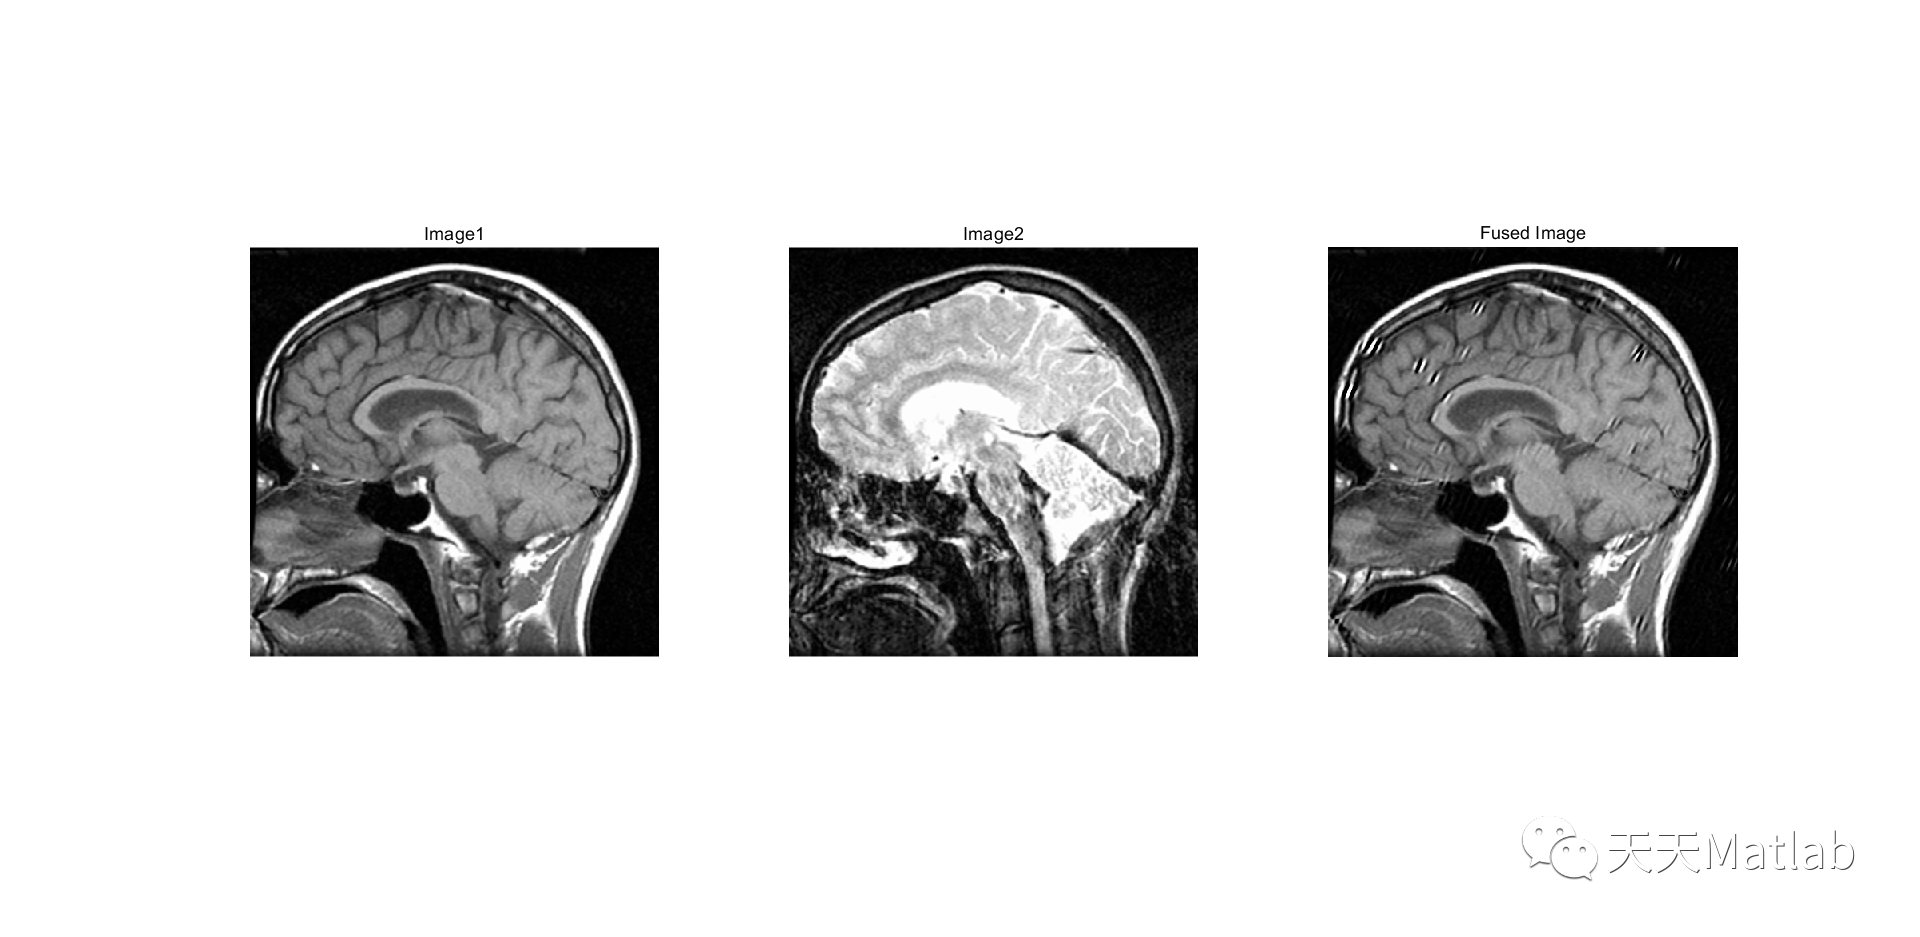

图像融合是计算机视觉领域的一个重要研究方向,旨在将多幅图像融合成一幅更具信息丰富度和视觉效果的图像。本文将介绍一种基于剪切变换和平均亮度的图像融合算法,并详细阐述其算法步骤。

图像融合算法的目标是将多幅图像中的有用信息进行合理的融合,以产生一幅更好的图像。该算法的步骤主要包括:图像预处理、剪切变换、亮度调整和图像合成。

最后是图像合成。在经过前面的步骤之后,可以将剪切变换和亮度调整后的图像进行融合。常用的图像融合方法有加权平均法和多分辨率融合法等。加权平均法是将待融合的图像按照一定的权重进行加权平均,得到最终的融合图像。多分辨率融合法是将图像分解成不同的分辨率层次,然后对每个层次进行融合,最后再进行重建。这些方法可以根据实际需求选择,以获得最佳的融合效果。

综上所述,基于剪切变换和平均亮度的图像融合算法是一种有效的图像融合方法。通过对图像进行剪切变换和亮度调整,以及采用合适的图像合成方法,可以得到一幅更具信息丰富度和视觉效果的融合图像。这种算法在计算机视觉领域有着广泛的应用前景,可以用于图像增强、目标检测等方面,具有重要的研究和实际价值。

addpath(genpath('ShearLab3D'))% 读取图像img1 = imread('c07_1.tif');img2 = imread('c07_2.tif');% 调整图像尺寸figure(1);img1 = imresize(img1,[512,512]);imshow(img1);title('Image1');figure(2);img2 = imresize(img2,[512,512]);imshow(img2);title('Image2');oeffs_fused,shearletSystem);% 显示融合图像figure(3);imshow(uint8(fused_image));title('Fused Image');% 原图像original1 = double(img1);original2 = double(img2);% Peak Signal-to-Noise Ratio (PSNR)% psnr1 = psnr(fused_image, original1);% psnr2 = psnr(fused_image, original2);psnr1 = calculate_psnr(fused_image, original1);psnr2 = calculate_psnr(fused_image, original2);fprintf('PSNR for image 1: %f\n', psnr1);fprintf('PSNR for image 2: %f\n', psnr2);% Structural Similarity Index (SSIM)ssim1 = ssim(fused_image, original1);ssim2 = ssim(fused_image, original2);fprintf('SSIM for image 1: %f\n', ssim1);fprintf('SSIM for image 2: %f\n', ssim2);% % Mean Squared Error (MSE)% mse1 = immse(fused_image, original1);% mse2 = immse(fused_image, original2);% fprintf('MSE for image 1: %f\n', mse1);% fprintf('MSE for image 2: %f\n', mse2);%% % Mean Absolute Difference (MAD)% mad1 = mean(abs(fused_image(:) - original1(:)));% mad2 = mean(abs(fused_image(:) - original2(:)));% fprintf('MAD for image 1: %f\n', mad1);% fprintf('MAD for image 2: %f\n', mad2);%% % NCC% ncc_value1 = NCC(fused_image, original1);% ncc_value2 = NCC(fused_image, original2);% fprintf('NCC for image 1: %f\n', ncc_value1);% fprintf('NCC for image 2: %f\n', ncc_value2);%% % MAE% mae_value1 = MAE(fused_image, original1);% mae_value2 = MAE(fused_image, original2);% fprintf('MAE for image 1: %f\n', mae_value1);% fprintf('MAE for image 2: %f\n', mae_value2);% Compute the standard deviationsd_fused = std(double(fused_image(:)));fprintf('SD of fused image: %f\n', sd_fused);% Spatial Frequencysf = mean(abs(diff(double(fused_image), 1, 1)), 'all') + mean(abs(diff(double(fused_image), 1, 2)), 'all');fprintf('Spatial Frequency of fused image: %f\n', sf);% Average Gradient[gradX, gradY] = gradient(double(fused_image));ag = mean(sqrt(gradX.^2 + gradY.^2), 'all');fprintf('Average Gradient of fused image: %f\n', ag);% Information Entropyie = entropy(fused_image);fprintf('Information Entropy of fused image: %f\n', ie);% Mutual Informationmi1 = mi(double(original1), double(fused_image));fprintf('Mutual Information of fused image and original image 1: %f\n', mi1);mi2 = mi(double(original2), double(fused_image));fprintf('Mutual Information of fused image and original image 2: %f\n', mi2);% Additional functionsfunction ncc = NCC(img1, img2)img1 = img1 - mean(img1(:));img2 = img2 - mean(img2(:));numerator = sum(sum(img1 .* img2));denominator = sqrt(sum(sum(img1 .^ 2)) * sum(sum(img2 .^ 2)));ncc = numerator / denominator;endfunction mae = MAE(target, reference)error = target - reference;mae = mean(abs(error(:)));end% Define the Mutual Information functionfunction h = mi(A,B)A = round((A - min(A(:))) / (max(A(:)) - min(A(:))) * 255);B = round((B - min(B(:))) / (max(B(:)) - min(B(:))) * 255);jointHistogram = accumarray([A(:) B(:)]+1, 1) / numel(A);jointEntropy = - sum(jointHistogram(jointHistogram > 0) .* log2(jointHistogram(jointHistogram > 0)));entropyA = entropy(uint8(A));entropyB = entropy(uint8(B));h = entropyA + entropyB - jointEntropy;endfunction psnr_val = calculate_psnr(img1, img2)img1 = double(img1);img2 = double(img2);mse = mean((img1(:) - img2(:)).^2);if mse == 0psnr_val = Inf;elsemaxValue = double(max(img1(:)));psnr_val = 20 * log10(maxValue/sqrt(mse));endend